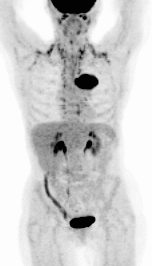

ПЭТ/КТ-диагностика – это один из важнейших инструментов для борьбы с онкологическими заболеваниями